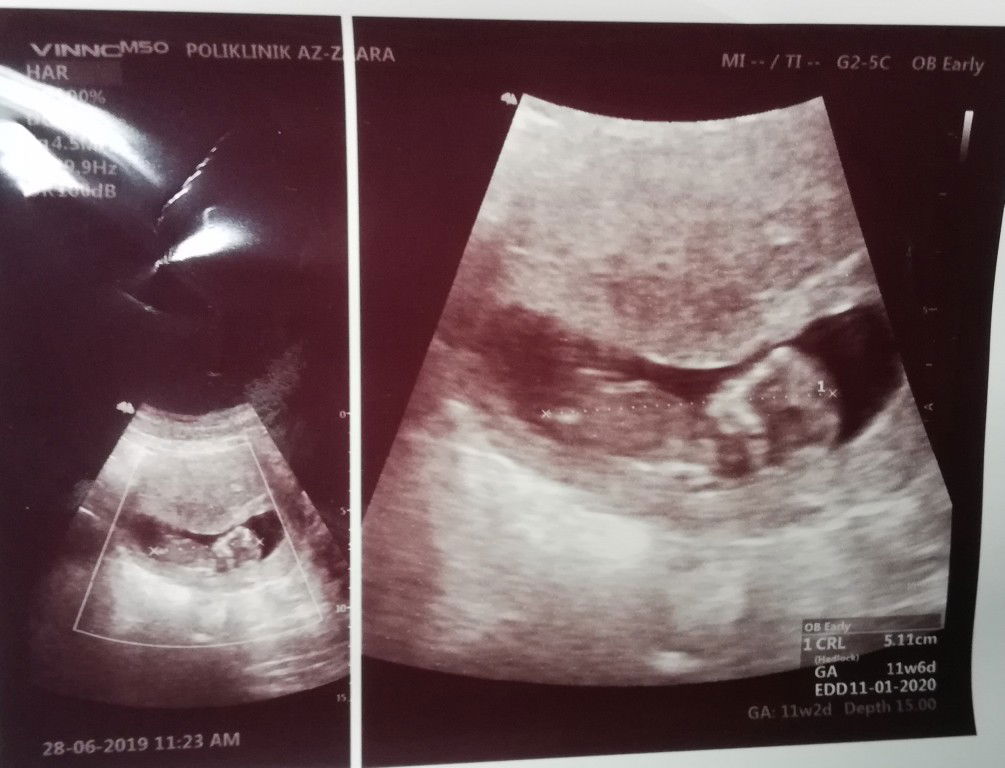

11 week 5 days

Alhamdulillah bby sihat.. Masa preg mggu ke 5-7 hari2 bleeding n spotting.. 4 doc jumpa.. Empat2 ckp 50-50.. Alhamdulillah baby kuat ?? ikut momy dia.. ? scan td walaupun tangan n kaki cenonett dok terkapai2, kepala dok angguk2.. Tak nak diam.. Hyper.. Doc pun gelak jee.. Geram je momy tgk.. Hope awak sihat setiap hari comey momy.. Aminnnn ?